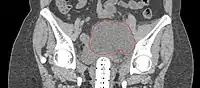

Lymphocele

- Seen postoperatively in up to 30% of GYN surgeries with pelvic/para-aortic LND

- Believed to arise from surgical transsection or inadequate ligation of draining lymphatics

- Lymphatic fluid may accumulate in various pelvic and retroperitoneal compartments

- Small lymphoceles typically resorb spontaneously

- Large lymphoceles may cause compression symptoms, and may result in abdominal distention, abdominal and pelvic pain, hydronephrosis, bladder dysfunction, constipation, tenesmus, edema of the ipsilateral leg and of the genitalia, and thromboembolism of iliac vessels

- Infection may cause fever, chills, and sepsis

- Symptomatic lymphoceles are typically managed initially with percutaneous CT-guided drainage, surgical therapy may be required

- Postoperative Lymphocele